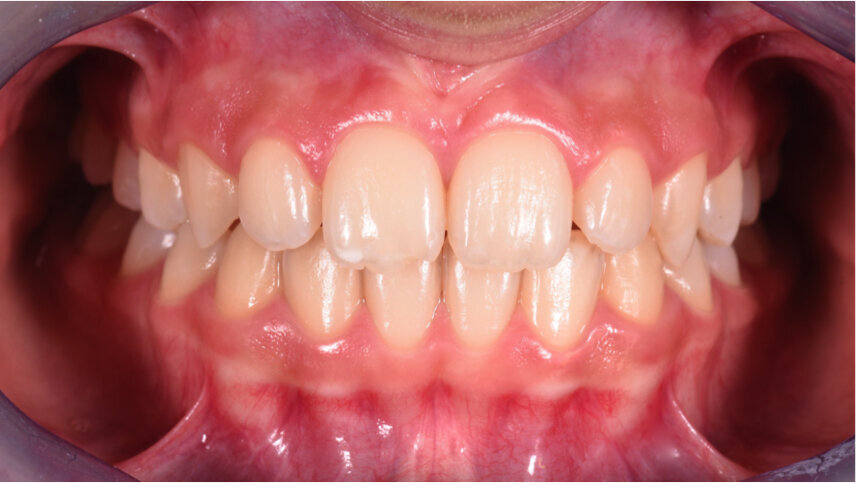

Caso 2 Paziente di anni 4, malocclusione dentale di III Classe, morso crociato monolaterale dx. La paziente viene trattata con dispositivo Amcop TC 2, il quale indossato tutte le notti e 1 ora di pomeriggio in 8 mesi risolve la malocclusione ripristinando il corretto rapporto occlusale; durante la terapia si riscontra un netto miglioramento della respirazione nasale e quindi il ripristino delle normali funzioni respiratorie. Il dispositivo, nei mesi successivi, viene indossato dalla paziente solo la notte per stabilizzare il caso e per guidare la crescita nel miglior modo possibile; all’età di 6 anni la paziente viene sottoposta a check-up ortodontico completo e quindi a panoramica e teleradiografia per poter analizzare anche la previsione di crescita e stabilire un eventuale step elastodontico (Figg. 15-23).

Fig. 15

Fig. 16

Fig. 17

Fig. 18

Fig. 19

Fig. 20

Fig. 21

Fig. 22

Fig. 23